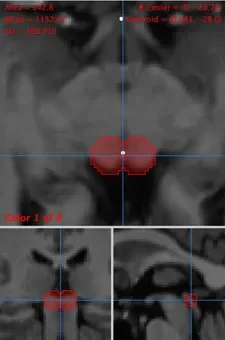

A team of Neurologists and Neuroradiologists, at St. Vincent’s University Hospital, identify the Superior Colliculus from fMRI images of one our participants.

Two spheres